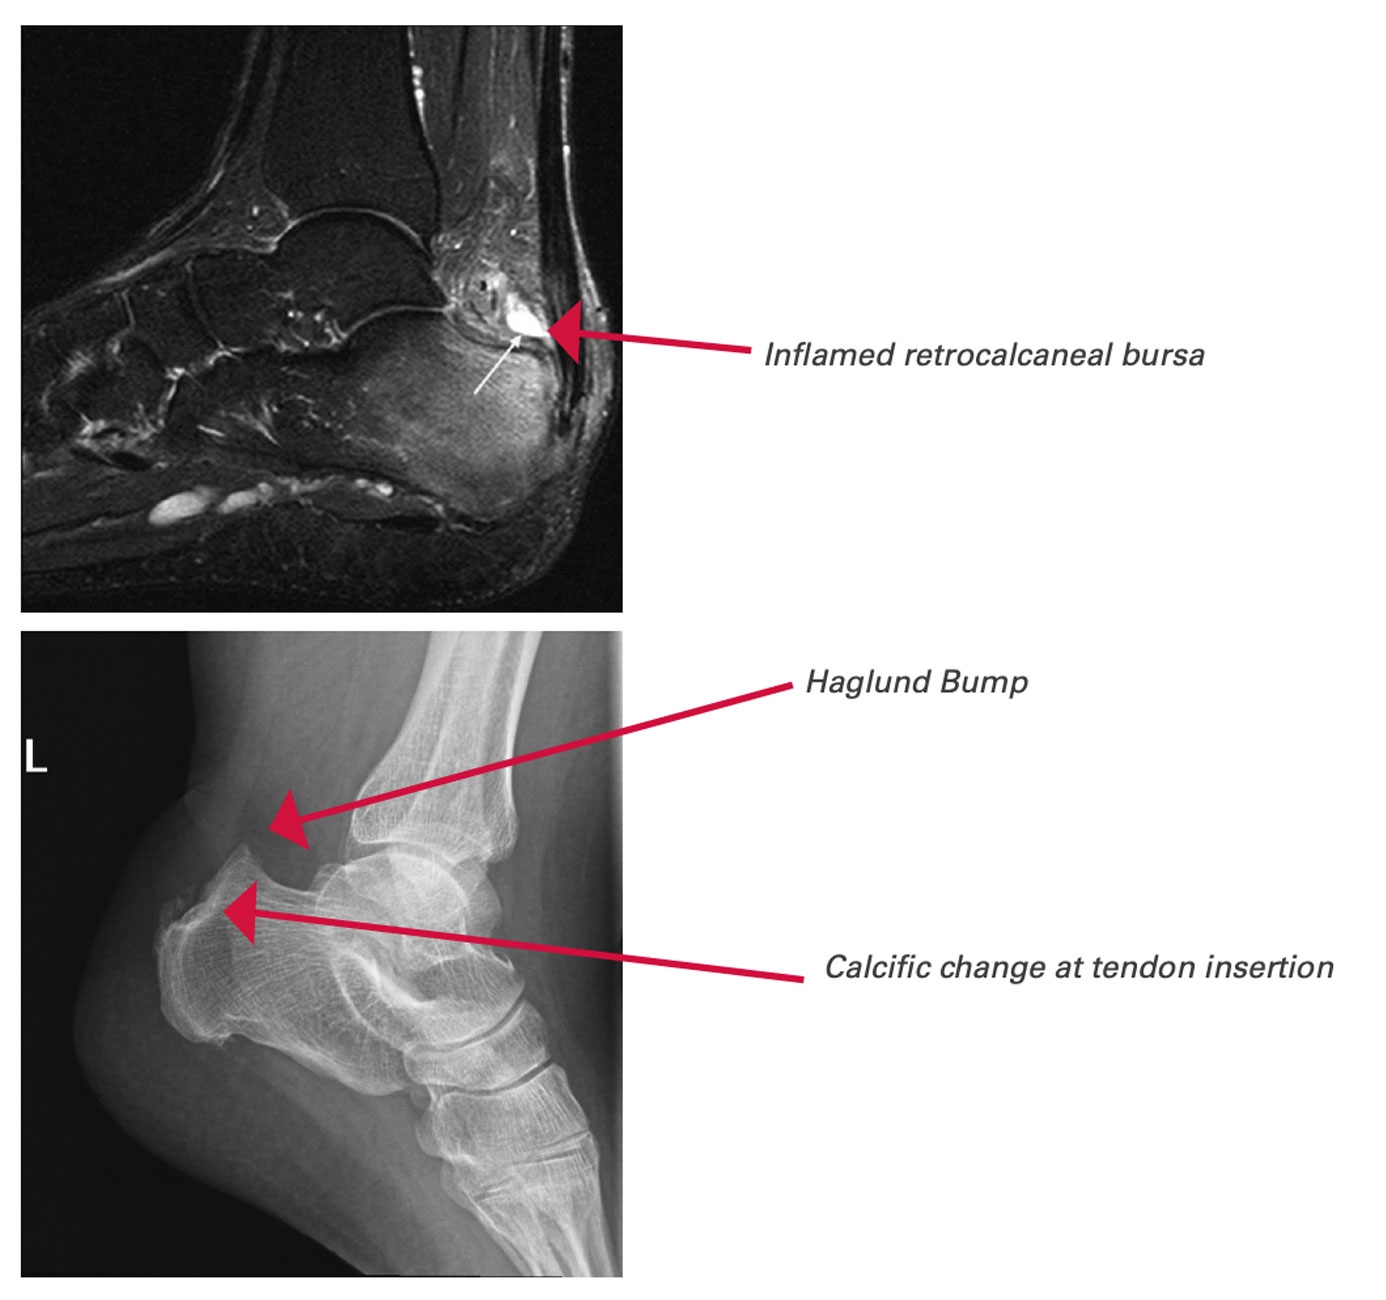

Achilles Tendon Pathology – Radsource

Achilles Tendinopathy | Mr Daniel Goldbloom | Melbourne

Retrocalcaneal Bursitis: Causes, Symptoms & Treatment

MRI Achilles Tendon – Melbourne Radiology

Achilles Tendon Pathology – Radsource

MRI Achilles Tendon – Melbourne Radiology

MRI Achilles Tendon – Melbourne Radiology

An ankle MRI demonstrates a sagittal STIR image of the Achilles tendon …

Radiodiagnosis – Imaging is Amazing-Interesting cases: Achilles tendon …